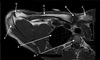

Perfectly

14

Q

What is letter D?

A

POSTERIOR LABRUM

How well did you know this?

1

Not at all